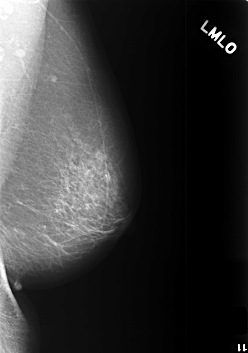

C_0412_1.LEFT_MLO

LEFT_MLO LINES 5640 PIXELS_PER_LINE 3960 BITS_PER_PIXEL 12 RESOLUTION 50 NON_OVERLAY